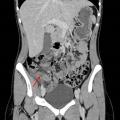

Avant l’ère des explorations radiologiques, la triade fièvre-défense en fosse iliaque droite-hyperleucocytose poussait à l’indication chirurgicale, avec un taux non négligeable (jusqu’à 25 %) d’appendicectomies effectuées sur un appendice sain. La réalisation systématique d’une imagerie abdominale a permis de diminuer significativement le taux d’appendicectomies inutiles. Les recommandations émises par les Sociétés françaises de chirurgie digestive et de radiologie préconisent donc la réalisation systématique d’une imagerie lors de la suspicion clinico-biologique d’appendicite aiguë (fig. 1).

Scanner abdominopelvien injecté : la référence

Le scanner abdominopelvien avec injection intraveineuse de produit de contraste est l’examen de référence, avec une excellente performance diagnostique. Il permet, dans le même temps, d’éliminer de nombreux diag­nostics différentiels et détermine la présence ou non d’une complication de l’appendicite, telle qu’un abcès ou une péritonite. Le diagnostic ­positif repose sur une augmentation du diamètre de l’appendice, une infiltration de la graisse périappendiculaire, un épaississement et une prise de contraste de ses parois (fig. 2).